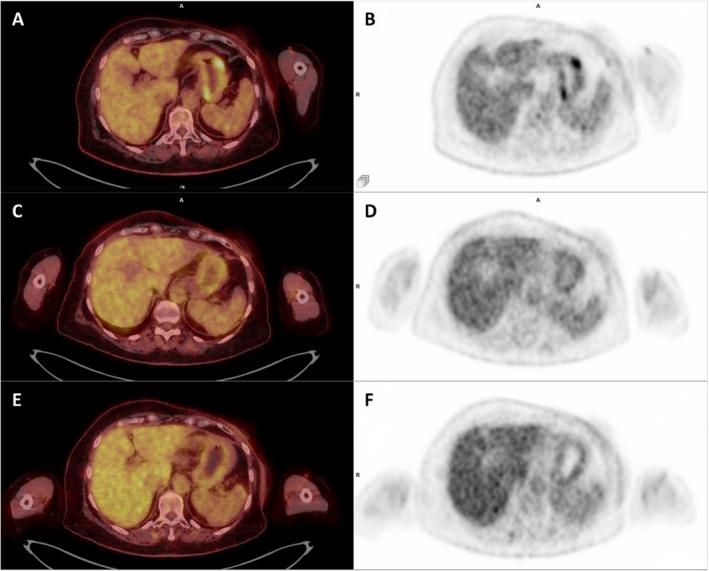

Invasive lobular carcinoma (ILC) of the breast is a rare subtype of breast cancer with distinct metastatic patterns. Although gastrointestinal metastases are rare, they can occur years after initial treatment. This case highlights the diagnostic challenges and management of late-onset gastric metastases. A 68-year-old woman with a history of ILC treated 20 years earlier presented with elevated tumor markers. [F]fluorodeoxyglucose positron emission tomography/computed tomography (FDG PET/CT) revealed hypermetabolic lesions in the stomach and esophagus in this patient with previously diagnosed gastritis and gastroesophageal reflux disease. Endoscopy and biopsies confirmed the presence of metastatic ILC in the stomach. Adjustment of treatment, including exemestane and everolimus, followed by paclitaxel and tamoxifen, resulted in partial disease control. Late-onset gastrointestinal metastases of ILC are uncommon and require special vigilance, particularly in patients with associated benign gastrointestinal pathologies, which may delay diagnosis. Persistent or new-onset gastrointestinal symptoms in breast cancer patients warrant thorough evaluation, including FDG PET/CT imaging and histological confirmation.

乳腺浸润性小叶癌(ILC)是一种罕见的乳腺癌亚型,具有独特的转移模式。尽管胃肠道转移很少见,但可在初始治疗数年之后发生。本病例突出了晚期胃转移的诊断挑战及处理方法。一名20年前曾接受过ILC治疗的68岁女性,出现肿瘤标志物升高。[F]氟脱氧葡萄糖正电子发射断层扫描/计算机断层扫描(FDG PET/CT)显示,该先前诊断为胃炎和胃食管反流病的患者,胃和食管出现代谢增高性病变。内镜检查及活检证实胃内存在转移性ILC。调整治疗方案,包括使用依西美坦和依维莫司,随后使用紫杉醇和他莫昔芬,实现了部分疾病控制。ILC的晚期胃肠道转移并不常见,需要特别警惕,尤其是对于伴有胃肠道良性病变的患者,这可能会延迟诊断。乳腺癌患者持续存在或新出现的胃肠道症状需要进行全面评估,包括FDG PET/CT成像及组织学确诊。